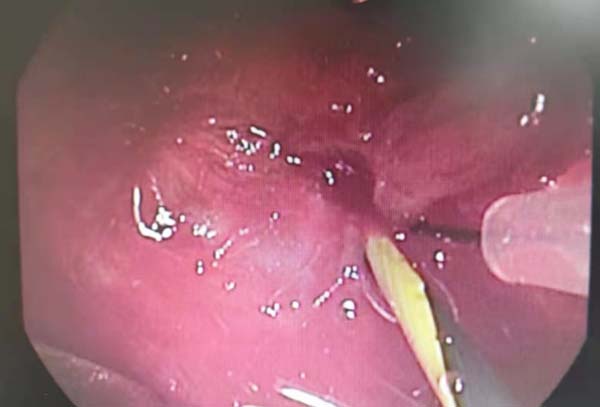

第一次气管镜镜下提示气管闭锁

插入导丝确定方向,电针切割瘢痕